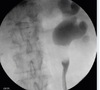

Describe what you see and what investigations would you like

I see the a Collimated view of a retrograde pyelogram focussing mostly on the left kidney and proximal ureter with a large filling defect I would proceed with selective cytology with barbotage FBC, U&E U-MC&S Book a CT IVP / 3phase CT ( if normal creat)